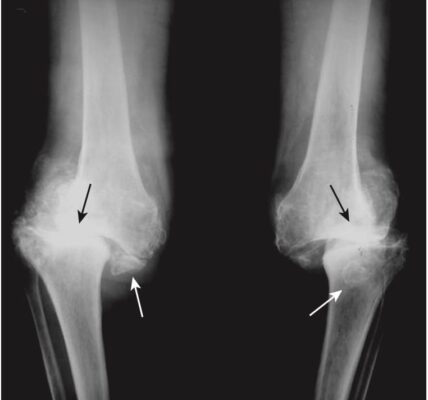

Hình 9. Bệnh khớp Charcot ở khớp gối do bệnh tiểu đường. Dấu hiệu đặc trưng của khớp Charcot là sự phân mảnh của xương xung quanh khớp, tạo ra nhiều mảnh xương nhỏ trong bao khớp (mũi tên trắng) và phá hủy khe khớp (mũi tên đen).